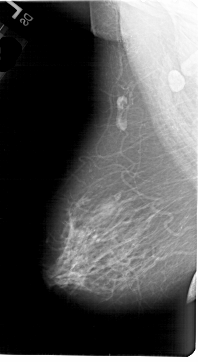

A_1646_1.RIGHT_MLO

RIGHT_MLO LINES 6331 PIXELS_PER_LINE 3736 BITS_PER_PIXEL 12 RESOLUTION 43.5 OVERLAY

FILE: A_1646_1.RIGHT_MLO.OVERLAY

TOTAL_ABNORMALITIES 1

ABNORMALITY 1

LESION_TYPE CALCIFICATION TYPE PLEOMORPHIC DISTRIBUTION CLUSTERED

ASSESSMENT 3

SUBTLETY 2

PATHOLOGY BENIGN